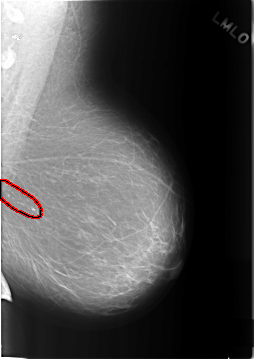

FILE: C_0317_1.LEFT_MLO.OVERLAY

TOTAL_ABNORMALITIES 1

ABNORMALITY 1

LESION_TYPE CALCIFICATION TYPE PLEOMORPHIC DISTRIBUTION CLUSTERED

ASSESSMENT 4

SUBTLETY 5

PATHOLOGY BENIGN

TOTAL_OUTLINES 1

BOUNDARY